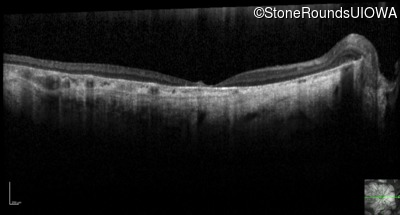

Optical Coherence Tomography - Right - 10/125 sc

Exemplar / OCT Stack